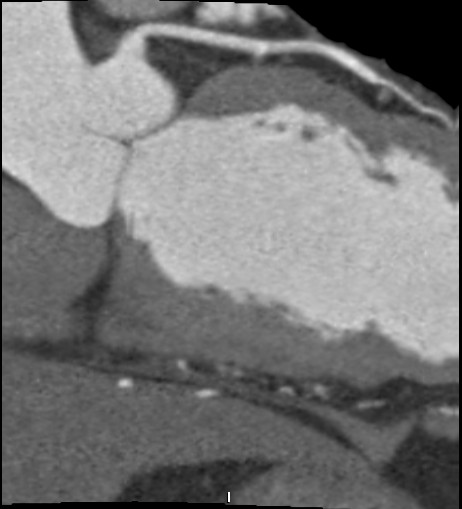

标题: CT24400:患者54岁,心前区不适进行心脏冠脉造影检查。 [打印本页]

标题: CT24400:患者54岁,心前区不适进行心脏冠脉造影检查。

患者54岁,心前区不适进行心脏冠脉造影检查。高手看看有问题没有?

图像很漂亮,好像未见异常